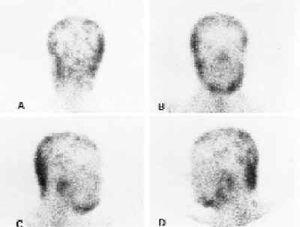

Gammagrafía Ga-67 en cadidiasis cutánea relacionada con el consumo de heroína.

Banzo, Montero, Uriarte, Vallina, Hernández, Guede, Pena, Quirce, Carril

Rev Esp Med Nucl Imagen Mol 1999;18:310-1